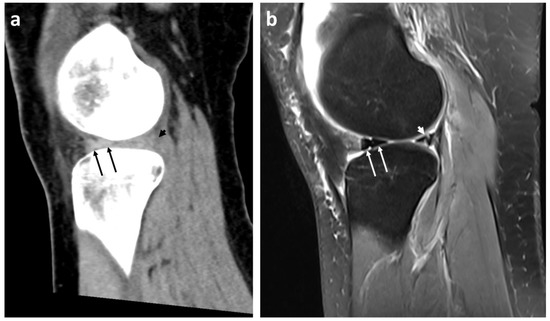

- Presence or absence (yes/no) of mentioned radiological signs of dislocated bucket handle meniscal tears (double delta sign, disproportional posterior horn sign, double PCL sign)